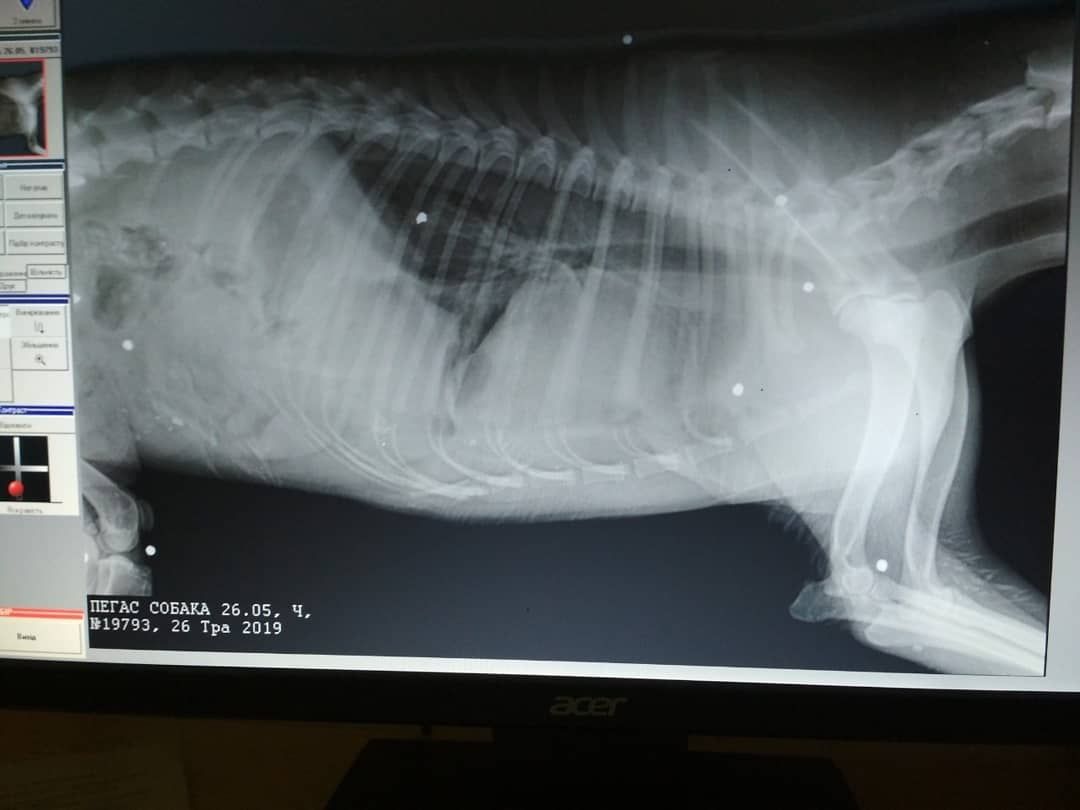

Сегодня волонтеры сообщили, что ночь пострадавшая пережила. Также были опубликованы рентгеновские снимки, на которых видна дробь в теле животного.